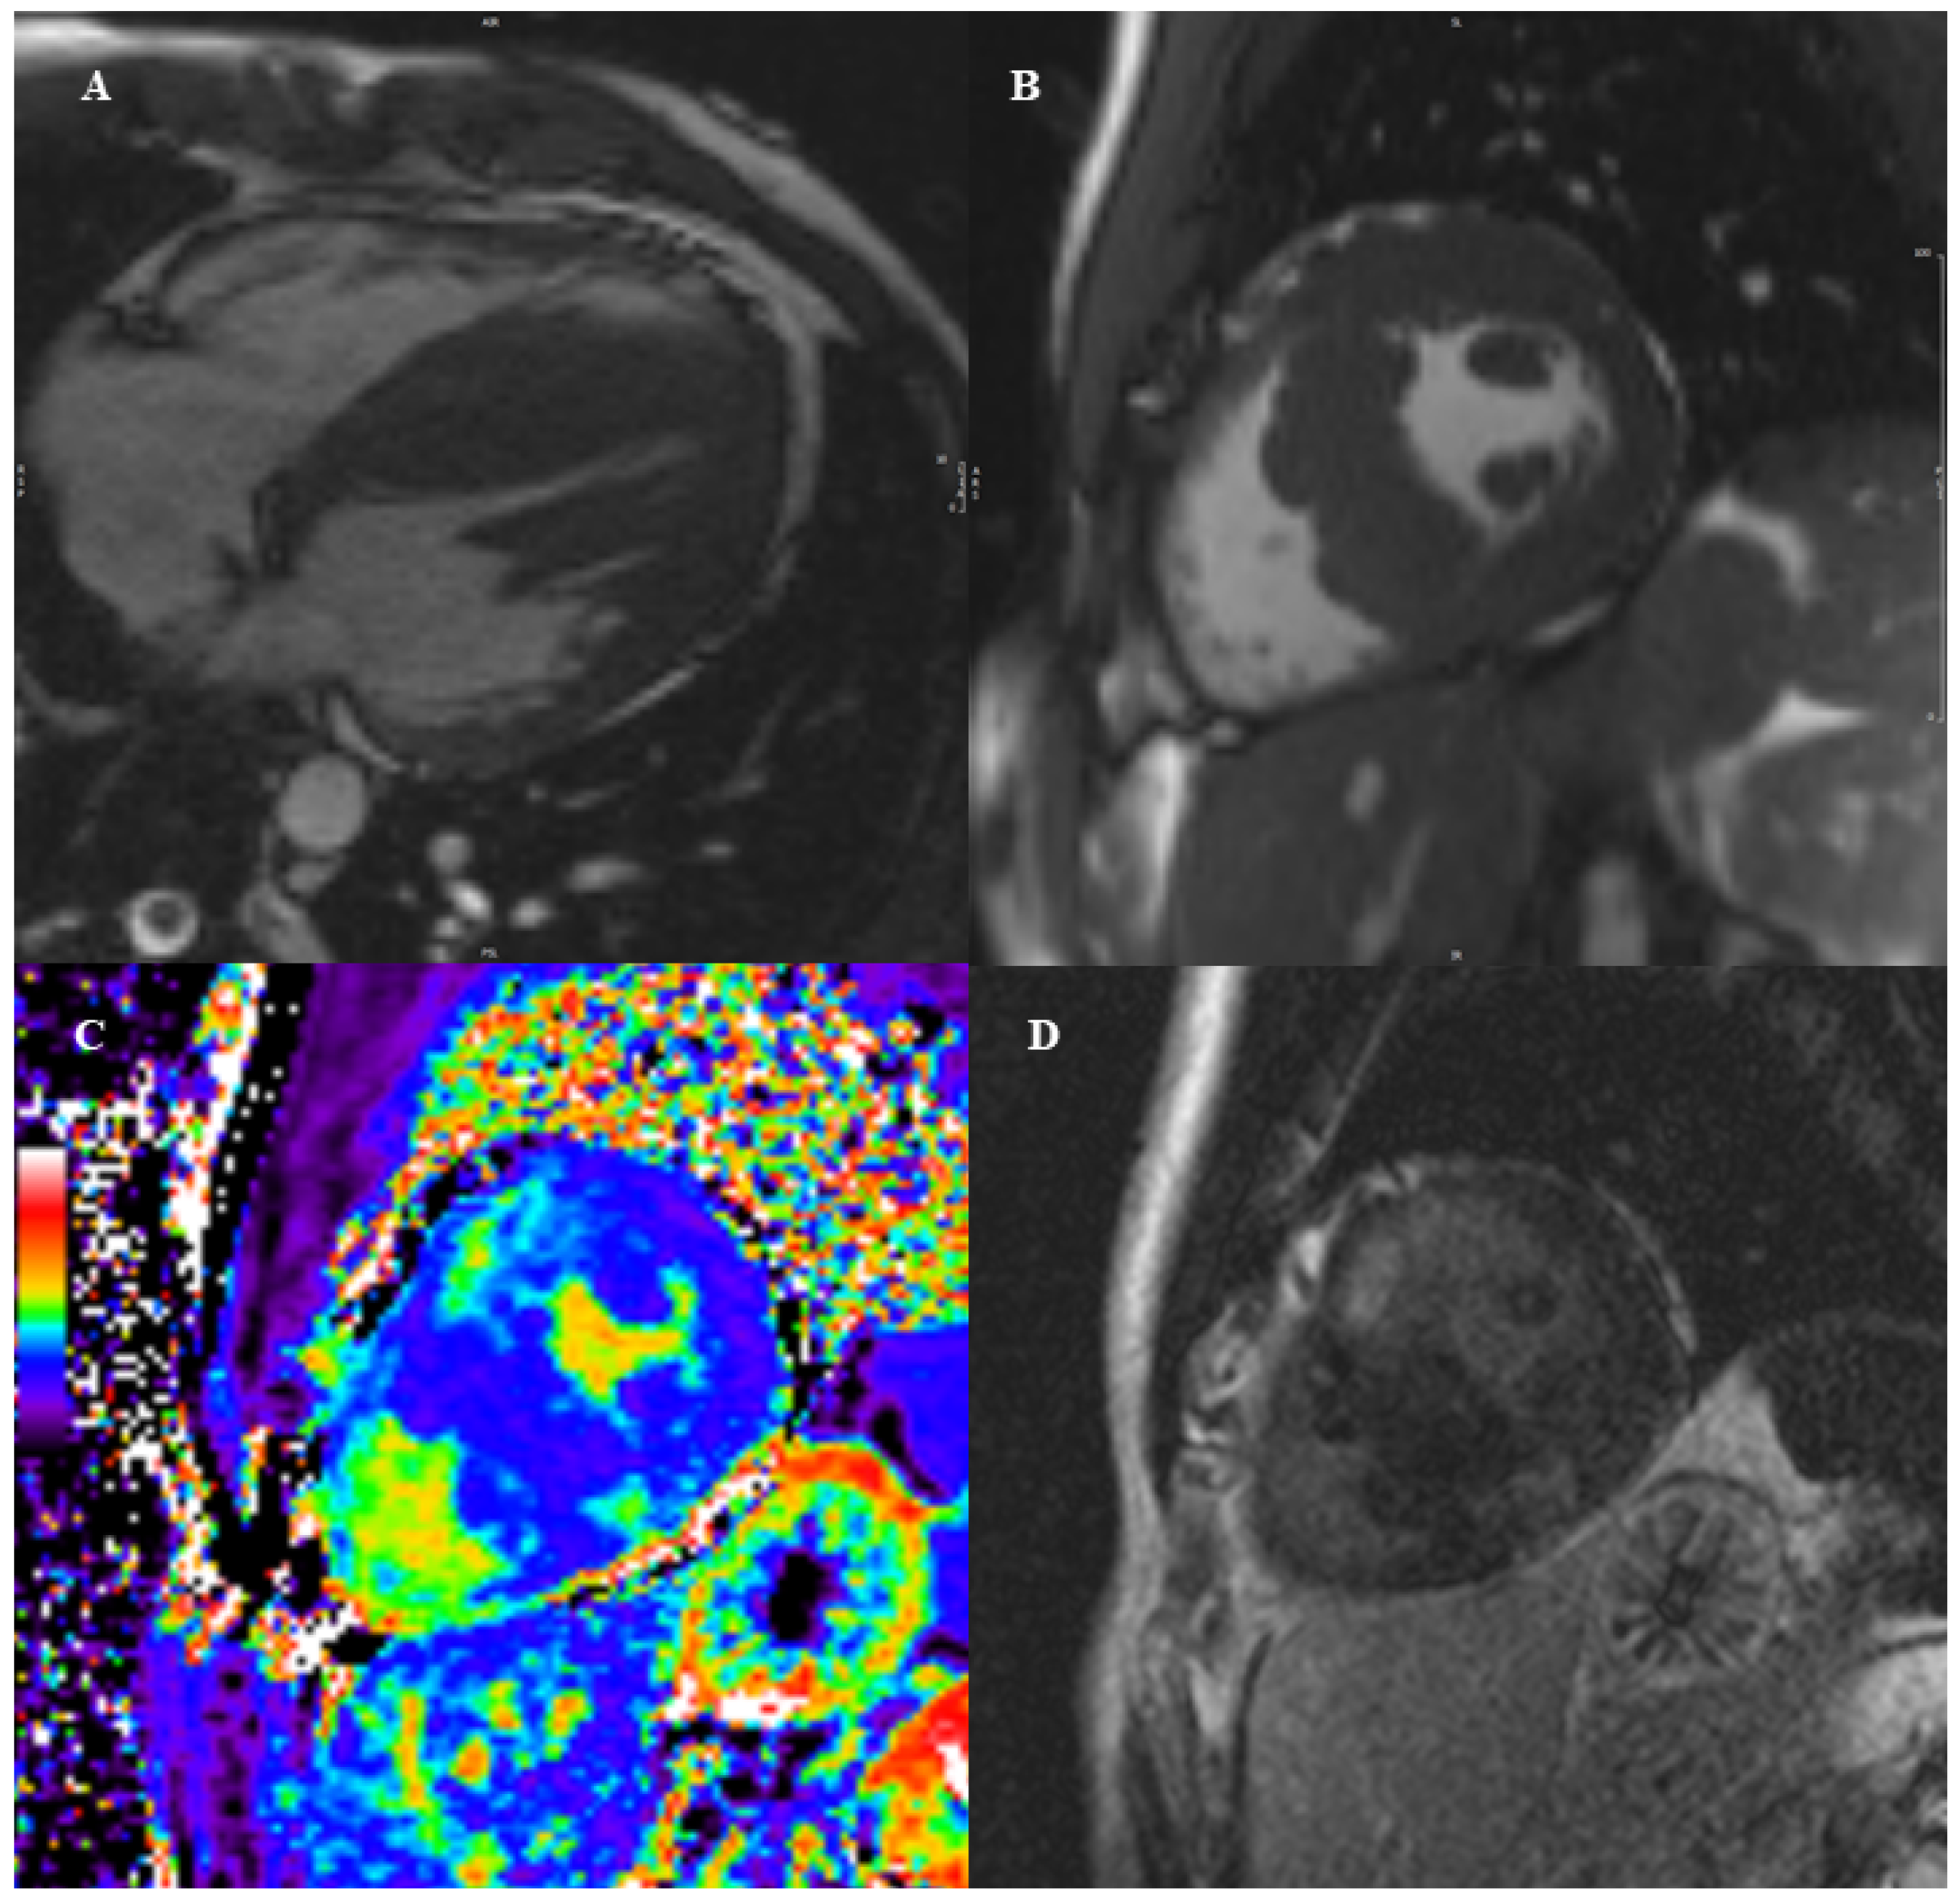

2. Brief Technical Aspects

3. Dilated Cardiomyopathy

CMR Diagnostic and Prognostic Role in Pediatric DCM